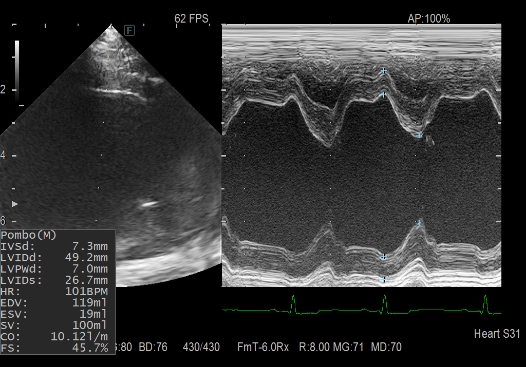

心臓超音波検査(心臓の大きさや弁、血管の異常の有無の評価)